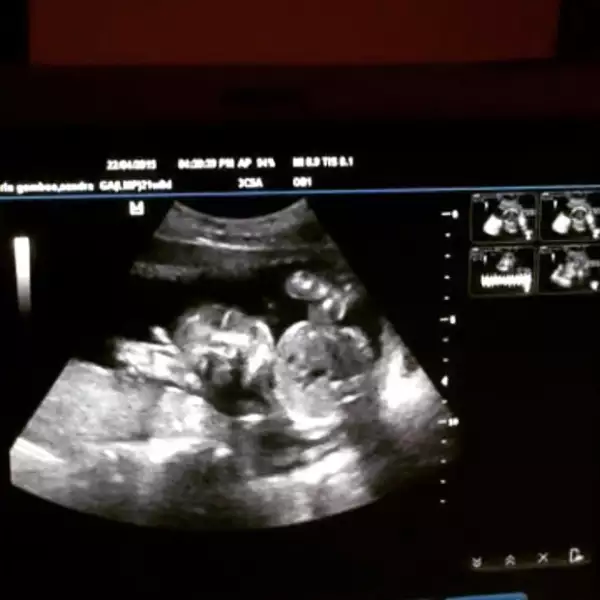

Como parte de su chequeo reglamentario, Sandra se realizó un ultrasonido, en el cual, no solo vio un bebé saludable, sino también un "saludo" de éste hacia sus padres, pues con la manita levantada, el bebé de 4 meses aparecía como si estuviera diciendo "hola".

Pero este gran momento no lo vivió sola, pues a través de una fotografía, la esposa de Leo de Lozanne compartió en su Instagram justo ese momento, el cual quedará para la posteridad en el corazón tanto de los orgullosos padres, como de sus fans, quienes al ver la fotografía no han dejado de colmar de bendiciones tanto al bebé como a la pareja.